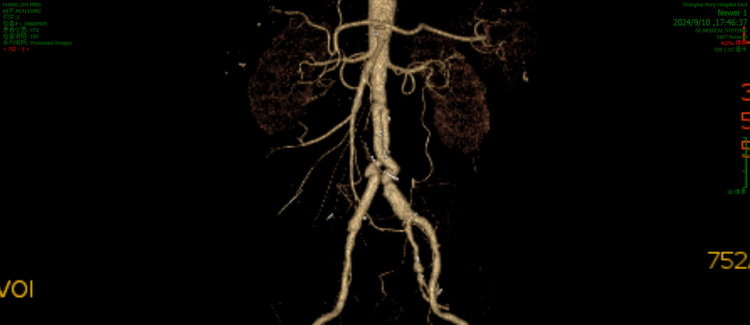

复查动脉CTA显示,股浅静脉组合血管与黄老伯的腹主动脉及髂动脉匹配良好,后腹膜没有异常渗出,手术效果令人满意。